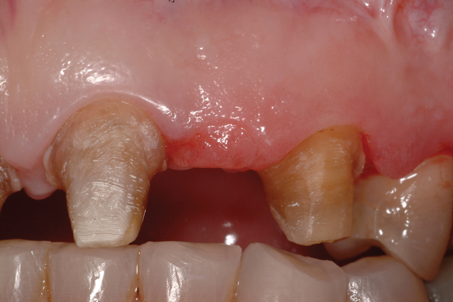

(8.) Retracted close-up view after removal of the defective fixed partial dentures.

Figure 8

A patient presented with two defective 3-unit fixed partial dentures spanning teeth Nos. 6 through 8 and teeth Nos. 9 through 11 (Figure 7). The defective fixed partial dentures were removed (Figure 8), an impression was made, and traditional provisional fixed partial dentures without ovate pontics were placed. After the impression was sent to the laboratory, the lab technician prepared ovate pontic sites on the stone cast (Figure 9) and fabricated the new definitive bridges. On the day of insertion, the provisional fixed partial dentures were removed (Figure 10), ovate pontic sites were prepared using a teardrop-shaped diamond bur (Figure 11), and the sites were sounded to confirm that there was at least 2 mm from the base of the pontic site to the alveolar bone (Figure 12). The fixed partial dentures were cemented, and the postoperative healing was uneventful (Figure 13).